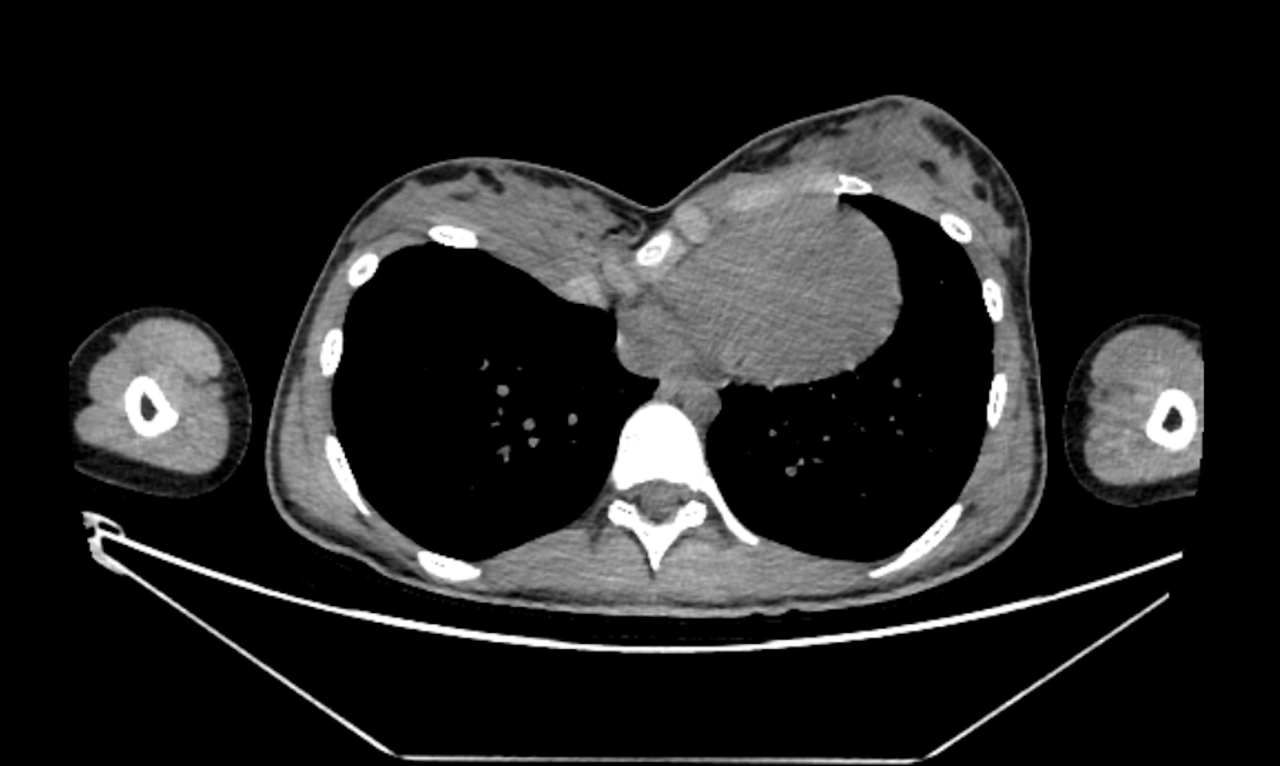

The CT scan confirms the clinical diagnosis. Correcting the bone deformity should be enough to treat the lack of breast volume. Other conventional treatments such as breast implants augmentation or fat grafting are impossible or inappropriate.

CT Scan of the Funnel Chest of a woman